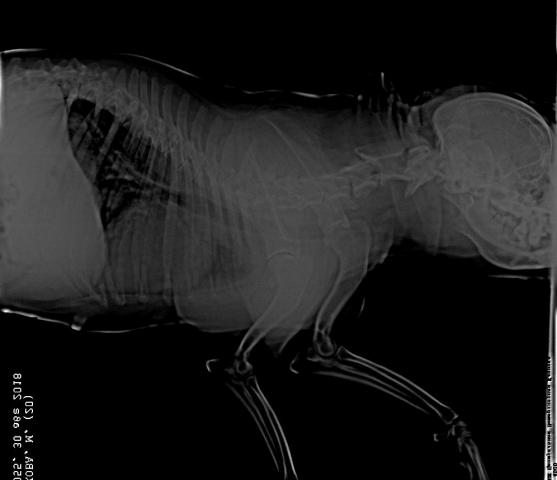

Французский бульдог,6 лет.Стала плохо ходить,что- то с позвоночником.Врачи не могут поставить диагноз.Есть снимки.Помогите!

Снимки хорошие, качественные, но совершенно не информативные. На этих пленках патология не определяется. Но здесь нет снимка, который нужен обязательно - поясничный отдел позвоночника в прямой проекции (такой, как 3-й, но только не шея, а поясница).

Нет,наоборот.Собака сначала стала немного наклонять голову вправо.Когда были на консультации у окулиста,то он обратил внимание на это ,сказал,что есть какие-то изменения в области шеи.Я отсутствовала дома 2 недели.Приехала,собаку вообще не узнала.Крен головы вправо стал еще сильнее,передние ноги как-то ослабли.Она идет,может споткнуться,упасть.Сходили,сделали рентген.снимок.Поставили диагноз:атланто-аксиальная нестабильность шейного отдела,спондилоартроз. Проколола 5 дней:актовегин,папаверин,комбилипн,мидокалм,дексаметазон. Пока делала уколы и еще дней 5 после этого собаке стало легче,а потом опять вернулись к тому, что было.На консультации врач сказал,что дальше просто колоть преднизалон. Я уехала к другому врачу,тот сделал снимки,которые я Вам отослала.Сказал, что диагноз не подтверждает,на пальцах показал, что со спинным мозгом все нормально.С помощью какой-то процедуры (бумаги на работе)обнаружил перфорацию барабанной перепонки.Выписал лечение:цефтриаксон,циклоферон,цебролизин(колола 2 дня,стало хуже),комбилипен.В уши-изотик.Сказал,что может быть у собаки был инсульт.Собаке от лечения хуже.Вот такие дела.